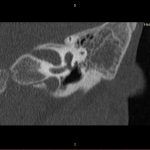

- Diagnosticul traumatismelor de bază de craniu

- Diagnosticul fracturilor:

- Complexe cranio-sinusale

- Complexe cranio-etmoidale

- Complexe cranio-orbitare

- Complexe cranio-faciale